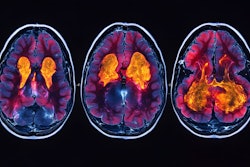

Nuclear Medicine Europe, an industrial association for nuclear medicine and molecular healthcare, on 24 September hosted its first-ever Nuclear Medicine Europe Day (#NMEUday), a pan-European awareness campaign.

The campaign highlighted the modality's role in healthcare and the challenges facing the field, and featured contributions from all five of Nuclear Medicine Europe’s working groups. The association conducted it primarily via LinkedIn.

Association leaders said the event aimed to inform the public about the nuclear medicine's life-saving effectiveness and to offer education regarding key issues such as infrastructure, workforce shortages, and supply stability. They also called for backing from legislators and policymakers to drive supportive regulation and investment.